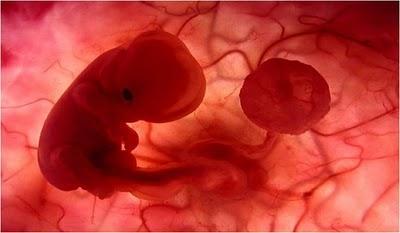

Las imágenes utilizadas en esta presentación son parte del documental "En el vientre materno" producido por National Geographic.

Son imágenes obtenidas a través de una micro-cámara introducida en el útero de una gestante. Gracias a las modernas técnicas fotográficas es posible acompañar el fascinante proceso de gestación de un bebé.

UN EMBRIÓN DE POCAS SEMANAS QUE SE ENCUENTRA EN EL INTERIOR DEL ÚTERO DE SU MADRE.

ESTÁ EN EL INICIO DE SU DESARROLLO.

ES APENAS EL PRINCIPIO DE UN SER HUMANO Y EN ESTE ESTADO PODRÍA SER CONFUNDIDO CON EL EMBRIÓN DE UN MACACO.

JUNTO A ÉL SE ENCUENTRA EL SACO VITELINO,PROPORCIONÁNDOLE LOS NUTRIENTES QUE NECESITAEN LAS PRIMERAS SEMANAS DE VIDA.

ALREDEDOR DE LA 8ª SEMANA DE GESTACIÓN EL SACO VITELINO PIERDE SUS FUNCIONES. EL CORDÓN UMBILICAL EMPEZARÁ AALIMENTARLO CON NUTRIENTES TOMADOS DELCUERPO MATERNO A TRAVÉS DE LA PLACENTA.

MIENTRAS TODO ESTO SUCEDE, ÉL FLOTA TRANQUILAMENTE,EN EL ÚTERO DE SU MADRE.